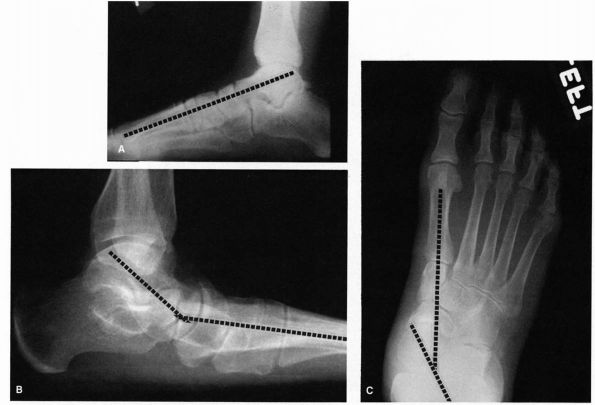

evaluation of a patient with pes planus are present irrespective of the

underlying cause. On the lateral radiograph, a line drawn through the

long axis of the talus should nearly bisect the navicular and first

metatarsal shaft (Figure 21-21). Mild flatfoot is indicated by a sag in this line of up to 15°; a sag from 15 to 40° indicates moderate flatfoot; and a sag greater than 40° indicates severe flatfoot.

In the AP radiograph, a line drawn through the long axis of the talus

and calcaneus should measure about 15°. An increase in this angle

indicates varying degrees of

flatfoot. Observation of the talonavicular joint demonstrates lateral subluxation of the navicular off the head of the talus (Figure 21-21).

![]() |

FIGURE 21-21. Radiographs of the flatfoot deformity. (A) Normal lateral radiograph demonstrating the relation between the long axis of the talus and first metatarsal. (B) In the flatfoot deformity, there is a sagging of the talonavicular joint. (C)

In the AP view, there should be a straight line relation between the long axis of the talus and first metatarsal. In flatfoot, this line is disrupted, and there is medial deviation of the head of the talus. |